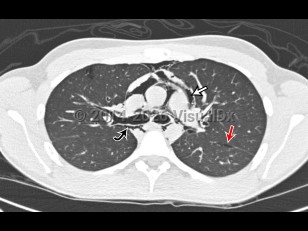

Pulmonary embolismPulmonary embolism

Aortic dissectionAortic dissection

Pulmonary edema

Pulmonary contusion